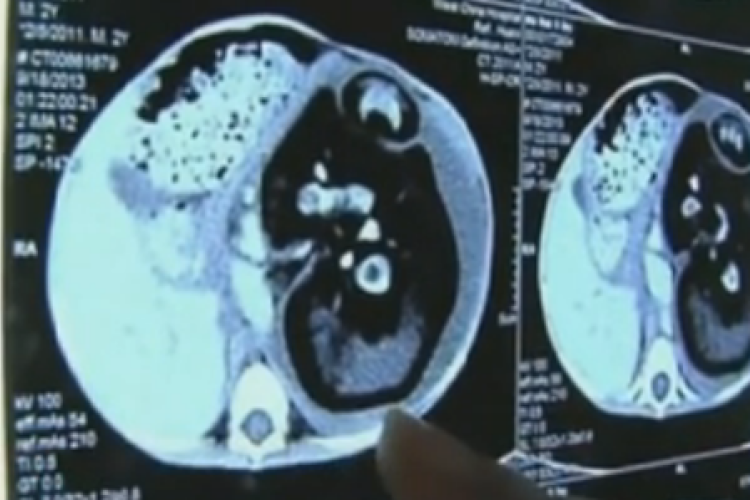

Térdén hordta a kézfejét egy kínai férfi, amíg vissza nem varrták a helyére

Átmenetileg a térdéhez oltották leszakadt kézfejét egy kínai férfinak, akit munkahelyi baleset ért.